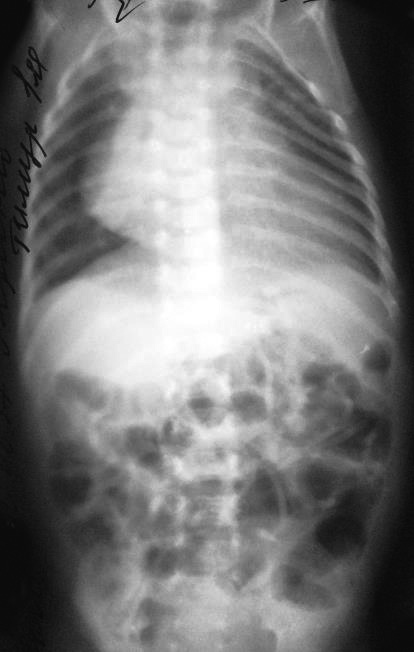

На 13-е сут после операции отмечалась отрицательная респираторная динамика – усиление втяжения грудной клетки, ослабление дыхания слева. По рентгенограмме – подозрение на левостороннюю диафрагмальную грыжу (рис. 8). Ребенок переведен на ИВЛ, начата интенсивная терапия в режиме предоперационной подготовки. По эхокардиограмме – декстракардия, расширение правых отделов сердца. Отмечались постоянные срыгивания при кормлении, проведена декомпрессия желудка, «голодная пауза». На рентгенографии ЖКТ с проходящим контрастом – перемещение части желудка и петель кишечника в передние отделы левой грудной полости, затемнение левых легочных полей (рис. 9).

Рис. 8. Рентгенограмма органов грудной клетки. Признаки левосторонней диафрагмальной грыжи.

Рис. 9. Рентгеноконтрастное исследование с пассажем контраста для подтверждения левосторонней диафрагмальной грыжи. Перемещение части желудка и петель кишечника в передние отделы левой грудной полости, затемнение левых